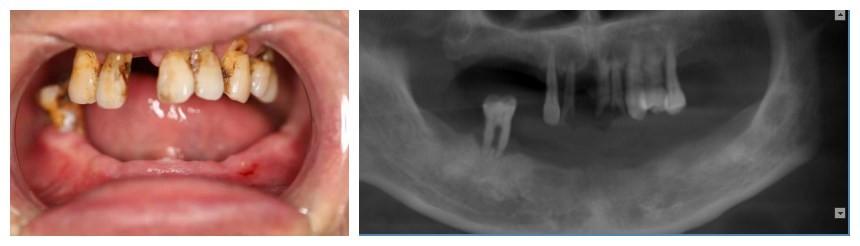

錢主任給予王先生口腔檢查,發(fā)現(xiàn)他有嚴(yán)重的牙周病,下頜牙基本全部脫落,上頜后牙也全部脫落只剩下幾顆松動(dòng)的前牙,根本無法咀嚼食物。給予口腔CT檢查后,錢主任發(fā)現(xiàn),王先生由于長期缺牙,牙槽骨已經(jīng)嚴(yán)重吸收,骨條件不理想,但鑒于王先生迫切的希望能盡快恢復(fù)美觀及咀嚼功能,經(jīng)過充分溝通及反復(fù)討論與完善調(diào)節(jié)計(jì)劃,終決定給予王先生一次性拔除全部松動(dòng)牙后行全口種植修復(fù)的方法,讓王先生在當(dāng)天種植術(shù)后當(dāng)天就能擁有一口整齊、漂亮的牙齒。

術(shù)前片